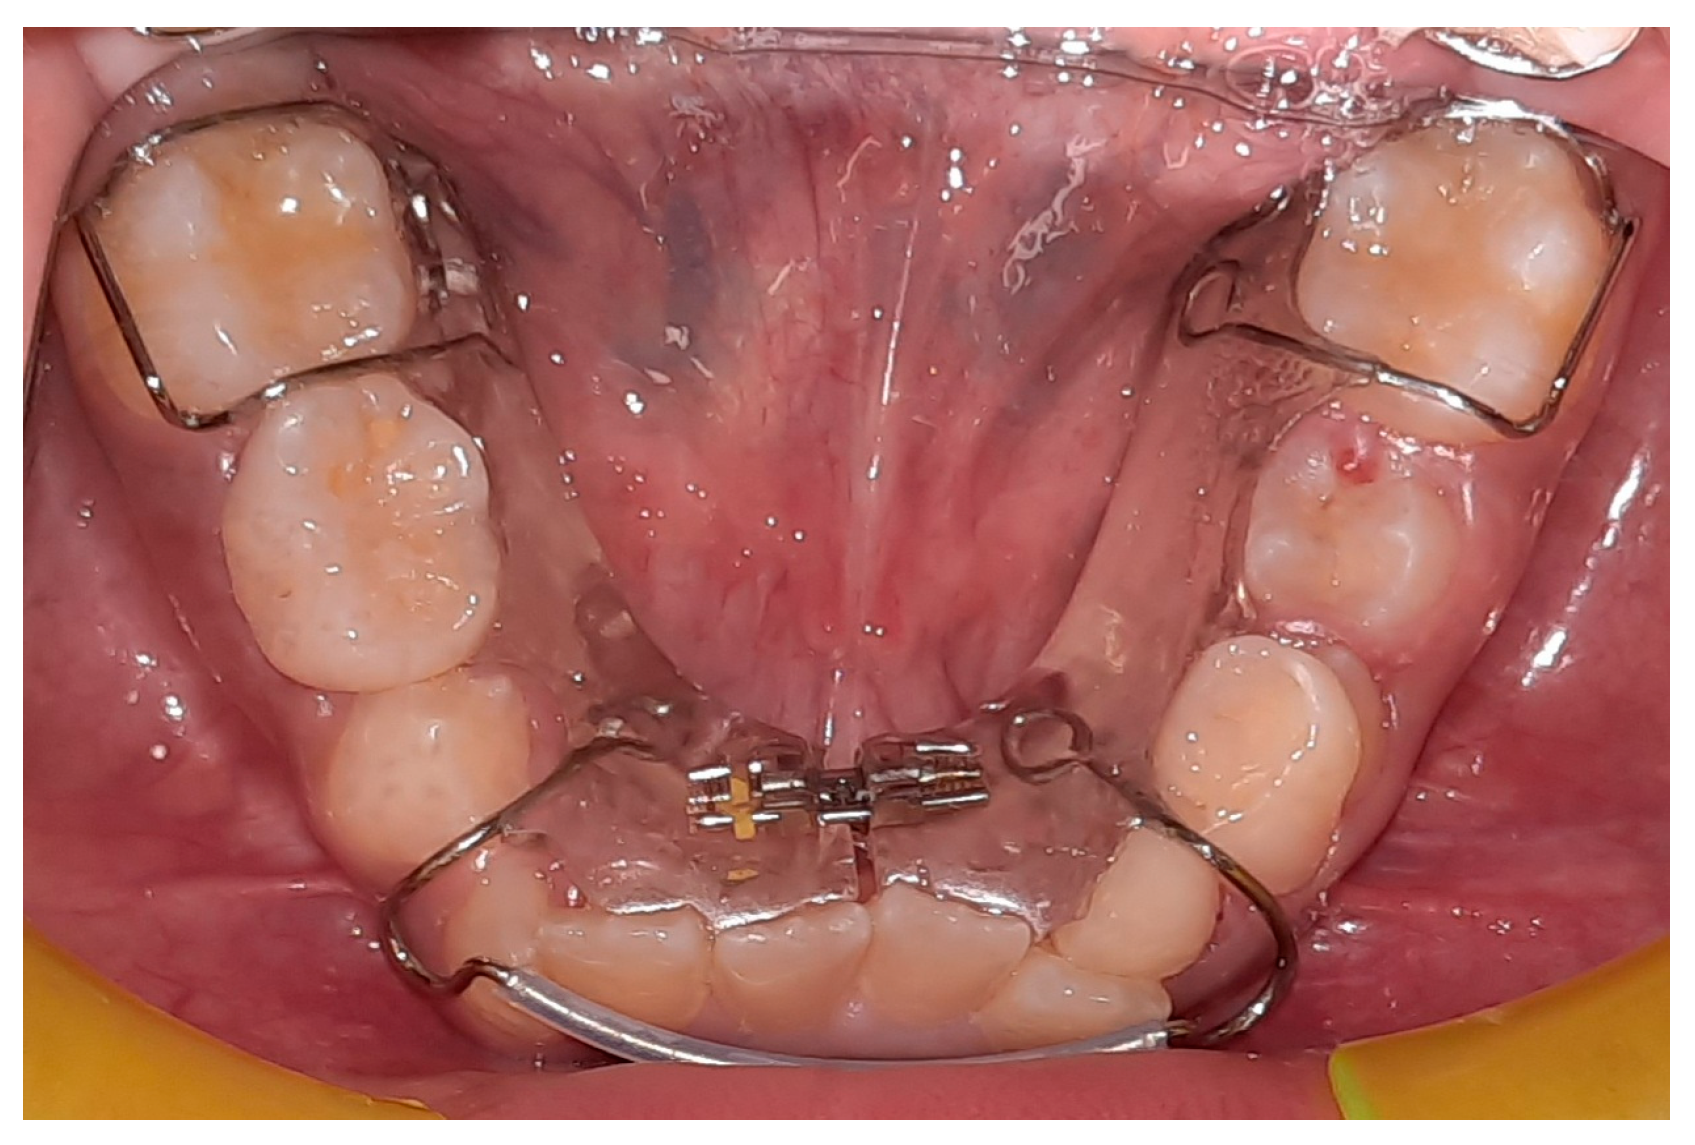

| Vincenzo Quinzi, Silvia Caruso et al., 2020 [27] | Prospective pilot study | This prospective study’s objective was to evaluate dental crowding and arch measurements before and after lip bumper versus Schwarz’s appliance therapy. | The present study investigated the pre- and post-treatment orthodontic records of 20 patients (10 males and 10 females). The following criteria were used for inclusion: first/second molar class malocclusion; mild to moderate (4–6 mm) crowding of the mandibular arch; mixed dentition; and age 9 years at the start of therapy. | Both a Schwarz appliance and a lip bumper are effective in lessening crowding in mixed dentition. The expansion of the dental arch is the reason for this improvement; however the two appliances’ allocation of the resulting space differed slightly. |

| Schwarz’s appliance Lip bumper appliance | To increment the perimeter of mandibular arch |